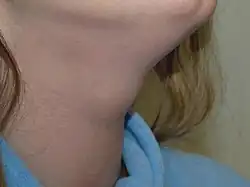

A thyroglossal cyst or thyroglossal duct cyst is a fibrous cyst that forms from a persistent thyroglossal duct. Thyroglossal cysts can be defined as an irregular neck mass or a lump which develops from cells and tissues left over after the formation of the thyroid gland during developmental stages.[1]

Thyroglossal cysts are the most common cause of midline neck masses and are generally located caudal to (below) the hyoid bone. These neck masses can occur anywhere along the path of the thyroglossal duct, from the base of the tongue to the suprasternal notch.[2] Other common causes of midline neck masses include lymphadenopathy, dermoid cysts, and various tooth development anomalies.[2]

Thyroglossal duct cysts most often present with a palpable asymptomatic midline neck mass usually below [65% of the time] the level of the hyoid bone. The mass on the neck moves during swallowing or on protrusion of the tongue because of its attachment to the tongue via the tract of thyroid descent. Some patients will have neck or throat pain, or dysphagia.

Thyroglossal cyst usually presents as a midline neck lump (in the region of the hyoid bone) that is usually painless, smooth and cystic, though if infected, pain can occur. There may be difficulty breathing, dysphagia (difficulty swallowing), or dyspepsia (discomfort in the upper abdomen), especially if the cyst becomes large.

The most common location for a thyroglossal cyst is midline or slightly off midline, between the isthmus of the thyroid and the hyoid bone or just above the hyoid bone. A thyroglossal cyst can develop anywhere along a thyroglossal duct, though cysts within the tongue or in the floor of the mouth are rare.A thyroglossal cyst will move upwards with protrusion of the tongue.Thyroglossal cysts are associated with an increased incidence of ectopic thyroid tissue. Occasionally, a lingual thyroid can be seen as a flattened strawberry-like lump at the base of the tongue.[3]